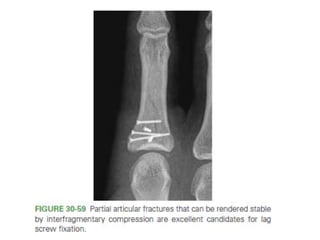

• #89 Figure 30-59 Partial articular fractures that can be rendered stable by interfragmentary compression are excellent candidates for lag screw fixation.

– ORIF – Lag screw fixation – if rotational instabiity.